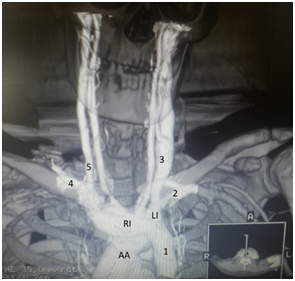

Figure 1 Left side, proximal section showing the junction of the left and right innominate veins (IL and IR respectively) to the left in the upper mediastinum. Right side, caudal section of the LSVC [1] origin.

A: Aortic Arch; T: Trachea; E: Esophagus